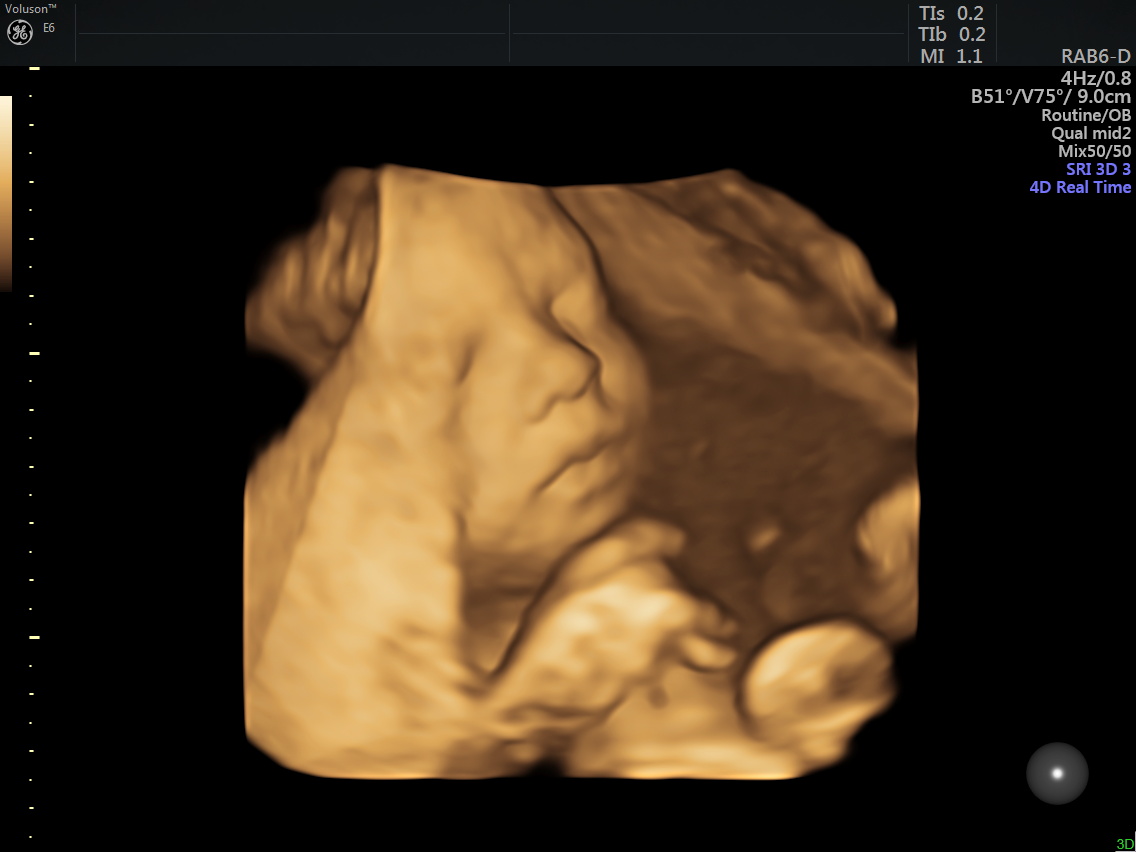

I’ve been sick off and on through this pregnancy but no complaints, just little uncomfortable here and there and little sleep, but I know the gift is so worth it. Little miss (name still being decided on by Ryken) is growing well, heart rate was 135-140 this week, and we got to see her beautiful face last week. Chubby cheeks and lots of sass already, and she looks a little like Ryken (no surprise there, she is technically her fraternal twin) – crazy to think right? Welcome to IVF and the incredible ability to freeze embryos. Little Miss has been growing well, despite the 2-vessel vs 3-vessel umbilical cord. My Dr says generally, they may slow down growth after 30ish weeks, so we will be doing a growth ultrasound in 2 weeks and monitoring her closely til she arrives!